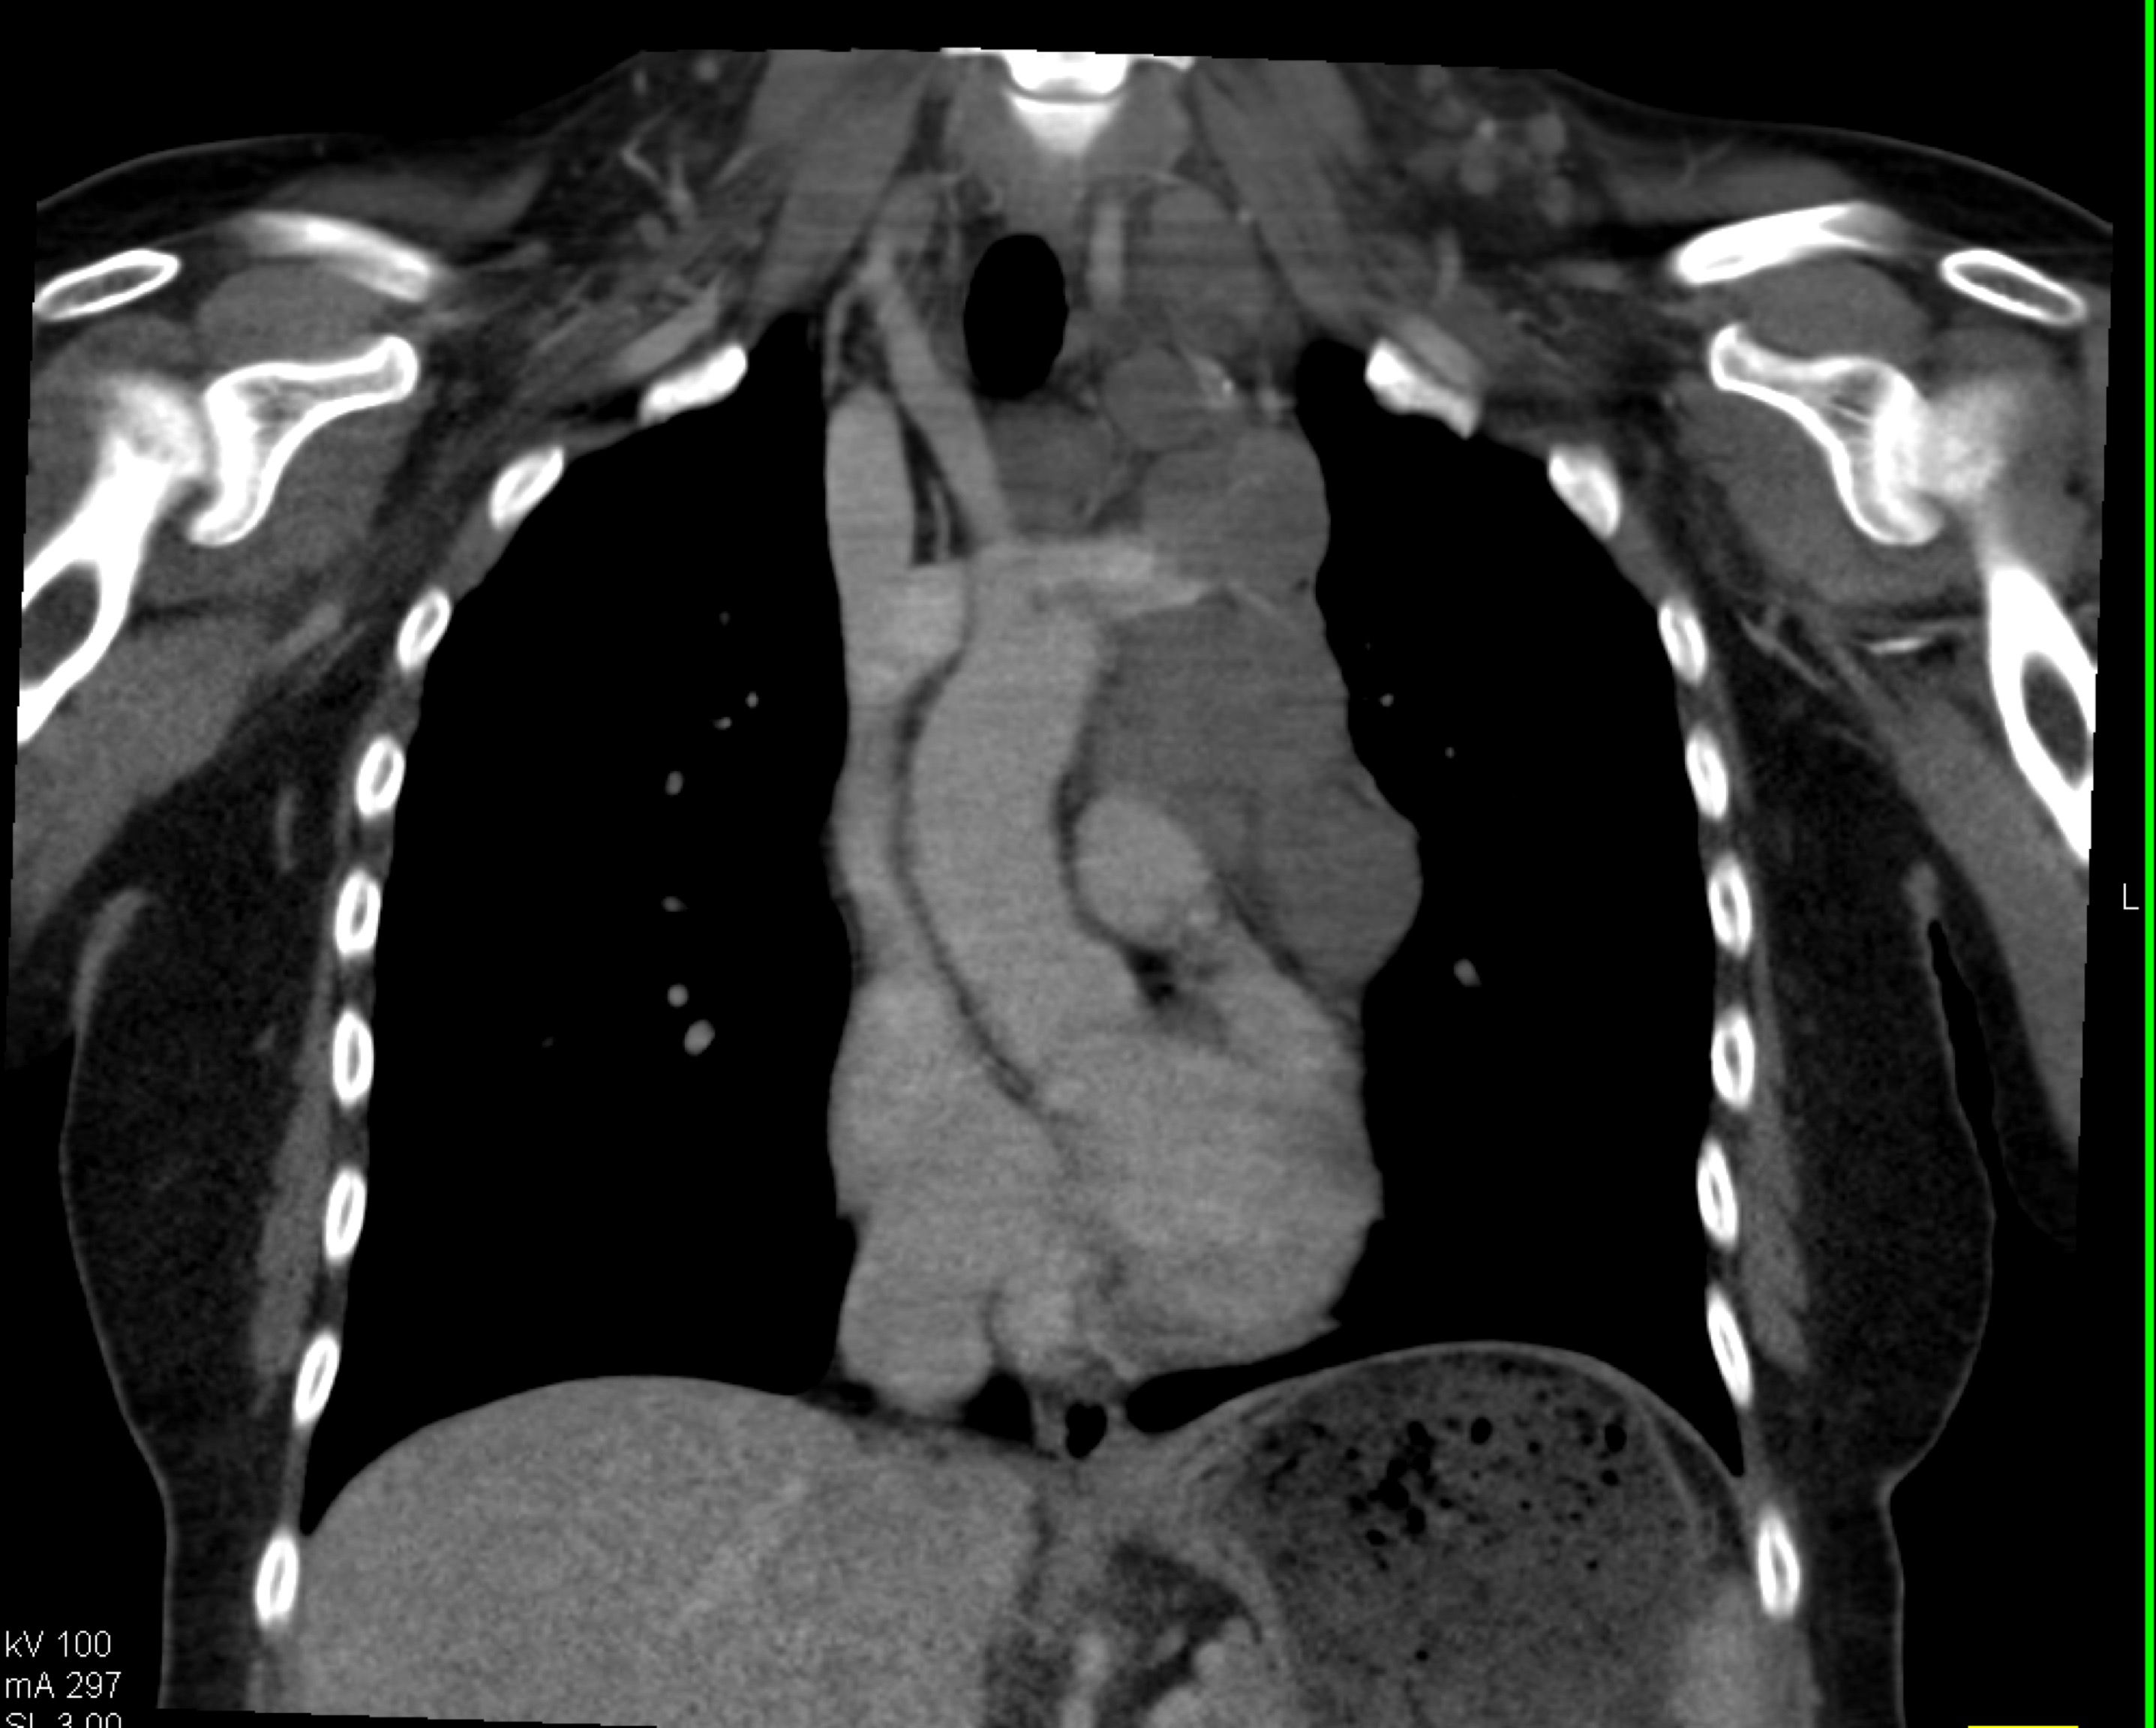

7) In this patient with mediastinal widening on CXR the best diagnosis is?

lymphoma

mediastinal lipoma

bronchogenic cyst

duplication cyst

8) In this patient with mediastinal widening on CXR the best diagnosis is?

germ cell tumor

lung cancer

teratoma